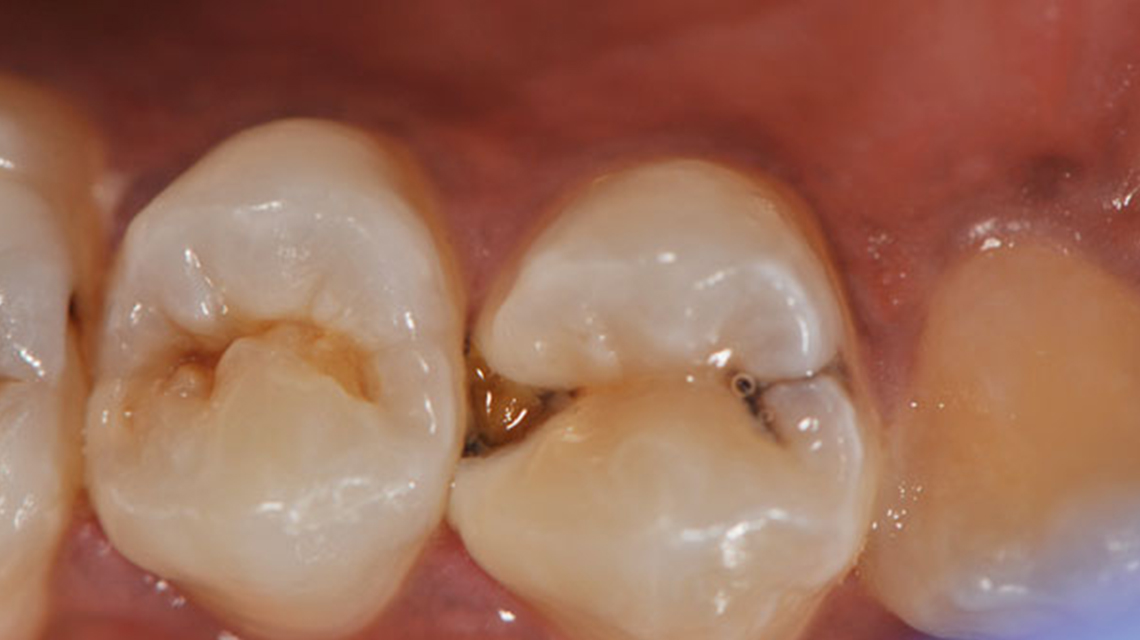

- Dental Caries is the teeth infection that result in dissolution and destruction of the calcified tissues of the tooth structure.

- It is essential to understand that cavitations in teeth (destruction of tooth surface,creating a ''CAVITY''or defect) are signs of bacterial infection.

- Carious lesions occur under a mass of bacteria capable of producing a sufficiently acidic environment to demineralize tooth structure.

Food Lodgement For Dental Caries

One of the main causes of food lodgment is the presence of ''gaps'' between teeth known as interdental spaces.

This gap can occur due to anatomical irregularities in the positioning of teeth/malocclusion, gum diseases, dental decay,partially erupted teeth,and other abnormal oral habits like tongue thrusting/thumb sucking.